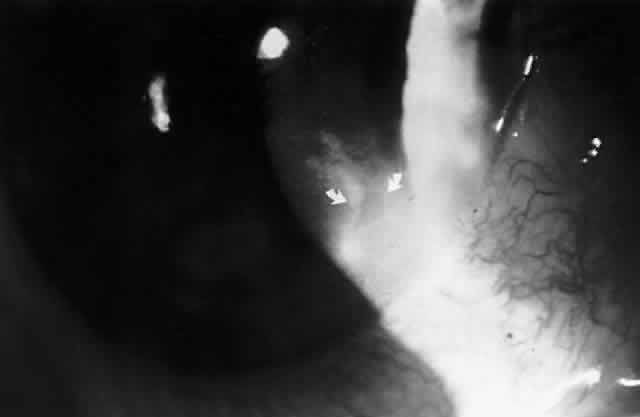

In 1990, Pflugfelder and associates reported a 66-year-old woman with bilateral, pleomorphic, ring-shaped, anterior stromal opacities which developed 3 months after initial onset of concurrent bilateral, dendritic epithelial keratitis (Fig. 5).74 Dendritic epithelium removed by impression cytology at the second recurrence of epithelial disease bound monoclonal antibody to EBV early antigen-diffuse and contained EBV genomic sequences as shown by PCR. Corneal epithelial cultures for HSV were negative on two occasions. EBV serology test did not indicate acute infection, and thus confirmed the earlier impression of Matoba and associates, that EBV keratitis may follow viral reactivation from the chronic carrier state.

Fig. 5. Peripheral corneal dendrite (arrows) in a 66-year-old woman who later developed ring opacities of the anterior corneal stroma.

The pathogenesis of EBV-associated keratitis has not been established; however, the case reported by Pflugfelder and associates74 suggests that epithelial infection by EBV may lead to stromal keratitis. EBV was demonstrated in the dendrite by PCR and EBV-specific monoclonal antibody staining. The epithelial keratitis began 4 days after a chemical facial peel. The chemoexfoliant included phorbol ester, which can induce EBV replication in latently infected B lymphocytes and epithelia and has been implicated as a cofactor in the development of nasopharyngeal carcinoma. Pflugfelder and associates suggested that the keratitis was due to phorbol ester-induced reactivation of EBV latent within corneal epithelium. Although the detection of EBV genome in this case may be due to persistently infected cells in the corneal epithelium, the immunohistochemical evidence of EBV early antigen within the dendritic epithelium indicates a replicative EBV infection was occurring and implicates EBV as the cause of the keratitis. Interestingly, among the patients with EBV stromal keratitis described by Matoba and associates,69 two patients were noted to have punctate epithelial granularity adjacent to stromal opacities. It is unknown whether these epithelial changes occurred as a result of recent EBV replication within the corneal epithelium or were secondary to underlying stromal inflammation.